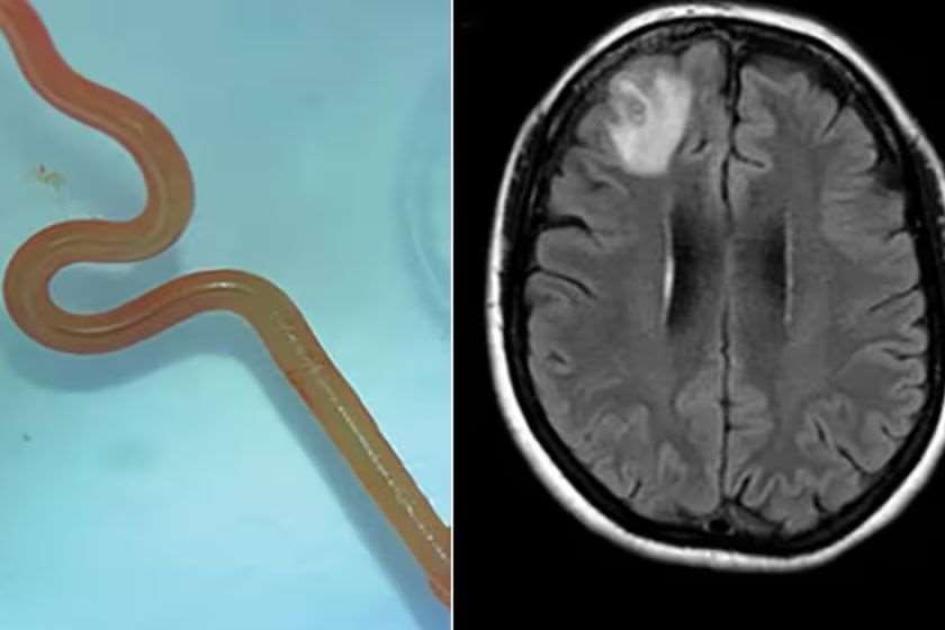

მეცნიერებმა ავსტრალიელი ქალის ტვინში ცოცხალი ჭია იპოვეს - ეს მსოფლიოში პირველი ასეთი შემთხვევაა. ამის შესახებ BBC წერს.

გამოცემის ინფორმაციით, წითელი პარაზიტის სიგრძე 8 სანტიმეტრი იყო.

„საოპერაციოში ყველას შოკი ჰქონდა, როდესაც ქირურგმა პაციენტის ტვინიდან ანომალია ამოიღო და ეს ანომალია ცოცხალი, 8-სანტიმეტრიანი წითელი ჭია აღმოჩნდა, რომელიც იკლაკნებოდა. ეს სრულიად ახალი ინფექციაა ადამიანში, რომელიც აქამდე არასოდეს ყოფილა დაფიქსირებული“, - ამბობს კანბერას ჰოსპიტლის ინფექციური დაავადებების ექიმი სანჯაია სენანაიაკე.

სპეციალისტების ვარაუდით, ქალი ჭიით Ophidascaris robertsi მაშინ დაინფიცირდა, როდესაც ავსტრალიაში, საკუთარი სახლის მახლობლად, ტბასთან მცენარეები მოაგროვა, რომლებიც შემდეგ საჭმლის მომზადებისთვის გამოიყენა.

ამის შემდეგ მას ინფექციის სიმპტომები დაეწყო: მუცლის ტკივილი, ხველა, ოფლიანობა და დიარეა. პაციენტი კლინიკაში 2021 წლის იანვარში მოხვდა. სკანირებამ გამოავლინა „ატიპიური დაზიანება თავის ტვინის მარჯვენა შუბლის წილში“. ამის მიზეზი კი მხოლოდ საოპერაციოში გამოავლინეს.